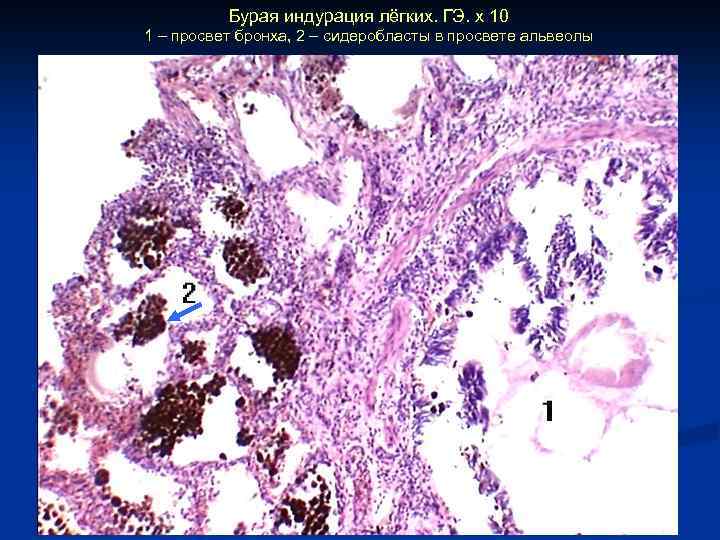

Бурая индурация лёгких. ГЭ. х 10 1 – просвет бронха, 2 – сидеробласты в просвете альвеолы